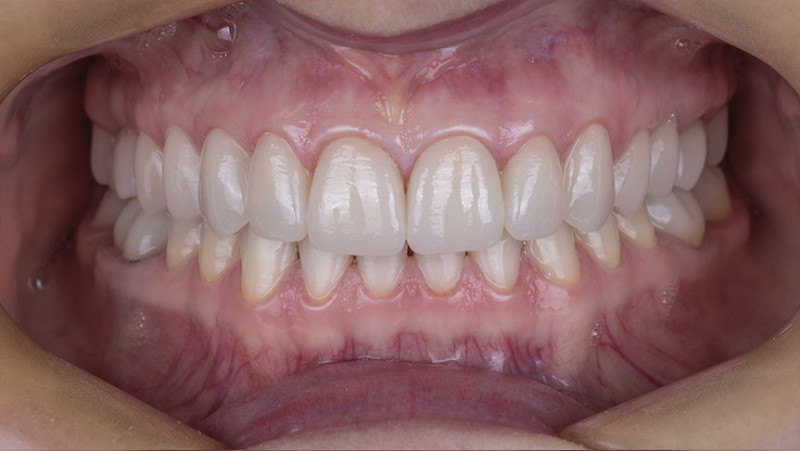

Установка керамической коронки

Установка керамических коронок на зубах и имплантатах.